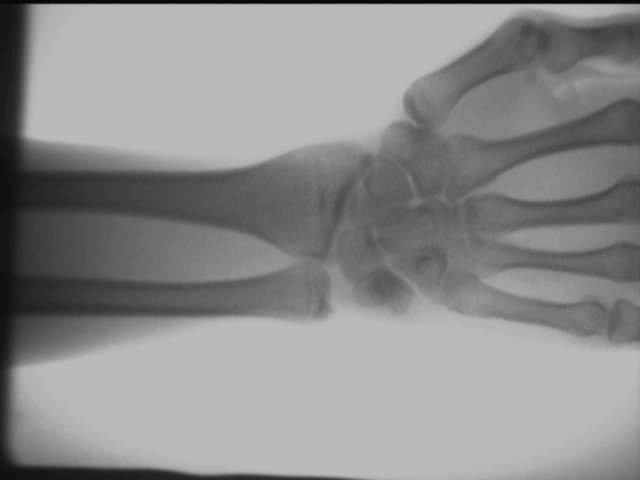

Ortopedik X-ışını dedektörünün yerinde test etki diyagramı

El ayak bileği eklemi etkisi

Yukarıdaki test sonuçları, AS-C200 kullanılarak yerinde elde edilmiştir.taşınabilir röntgen cihazı